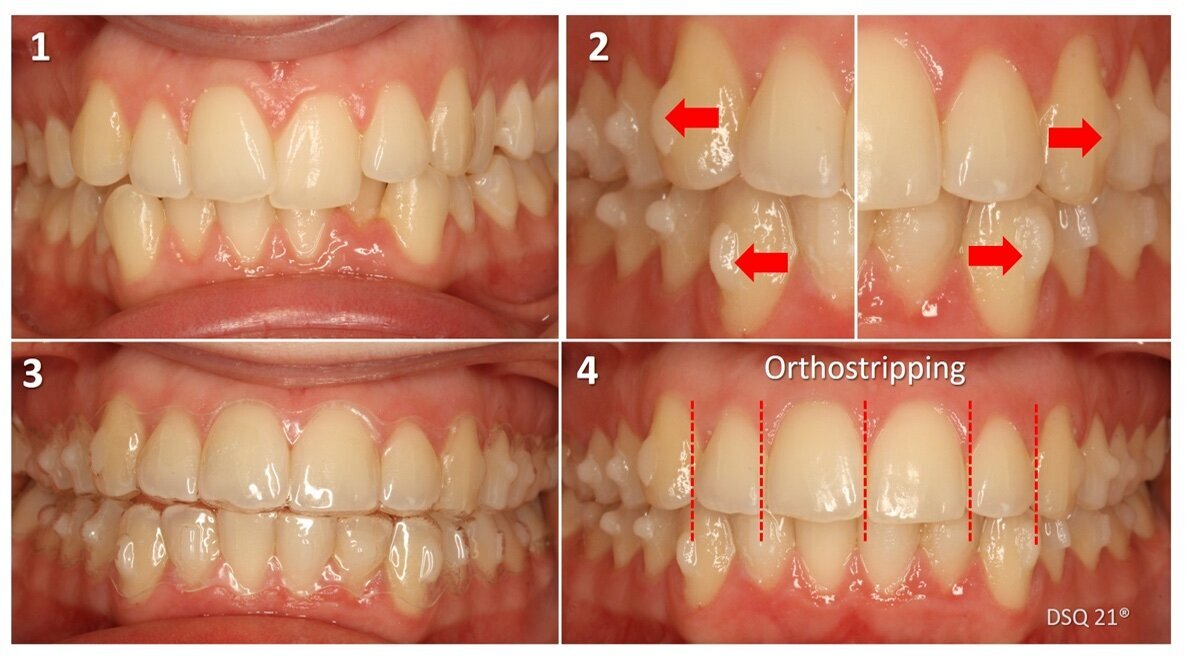

Caso clínico tratado con alineadores, ataches activos de rotación de cuarto de esfera en caninos y orthostripping de 0,75 mm/diente en la parte anterior de la arcada superior.

Caso tratado con alineadores, ataches activos de rotación de cuarto de esfera en caninos y orthostripping de 0,75 mm/diente en la parte anterior de la arcada superior (figura 30).

Figura 30. Caso clínico tratado con alineadores, ataches activos de rotación de cuarto de esfera en caninos y orthostripping de 0,75 mm/diente en la parte anterior de la arcada superior.